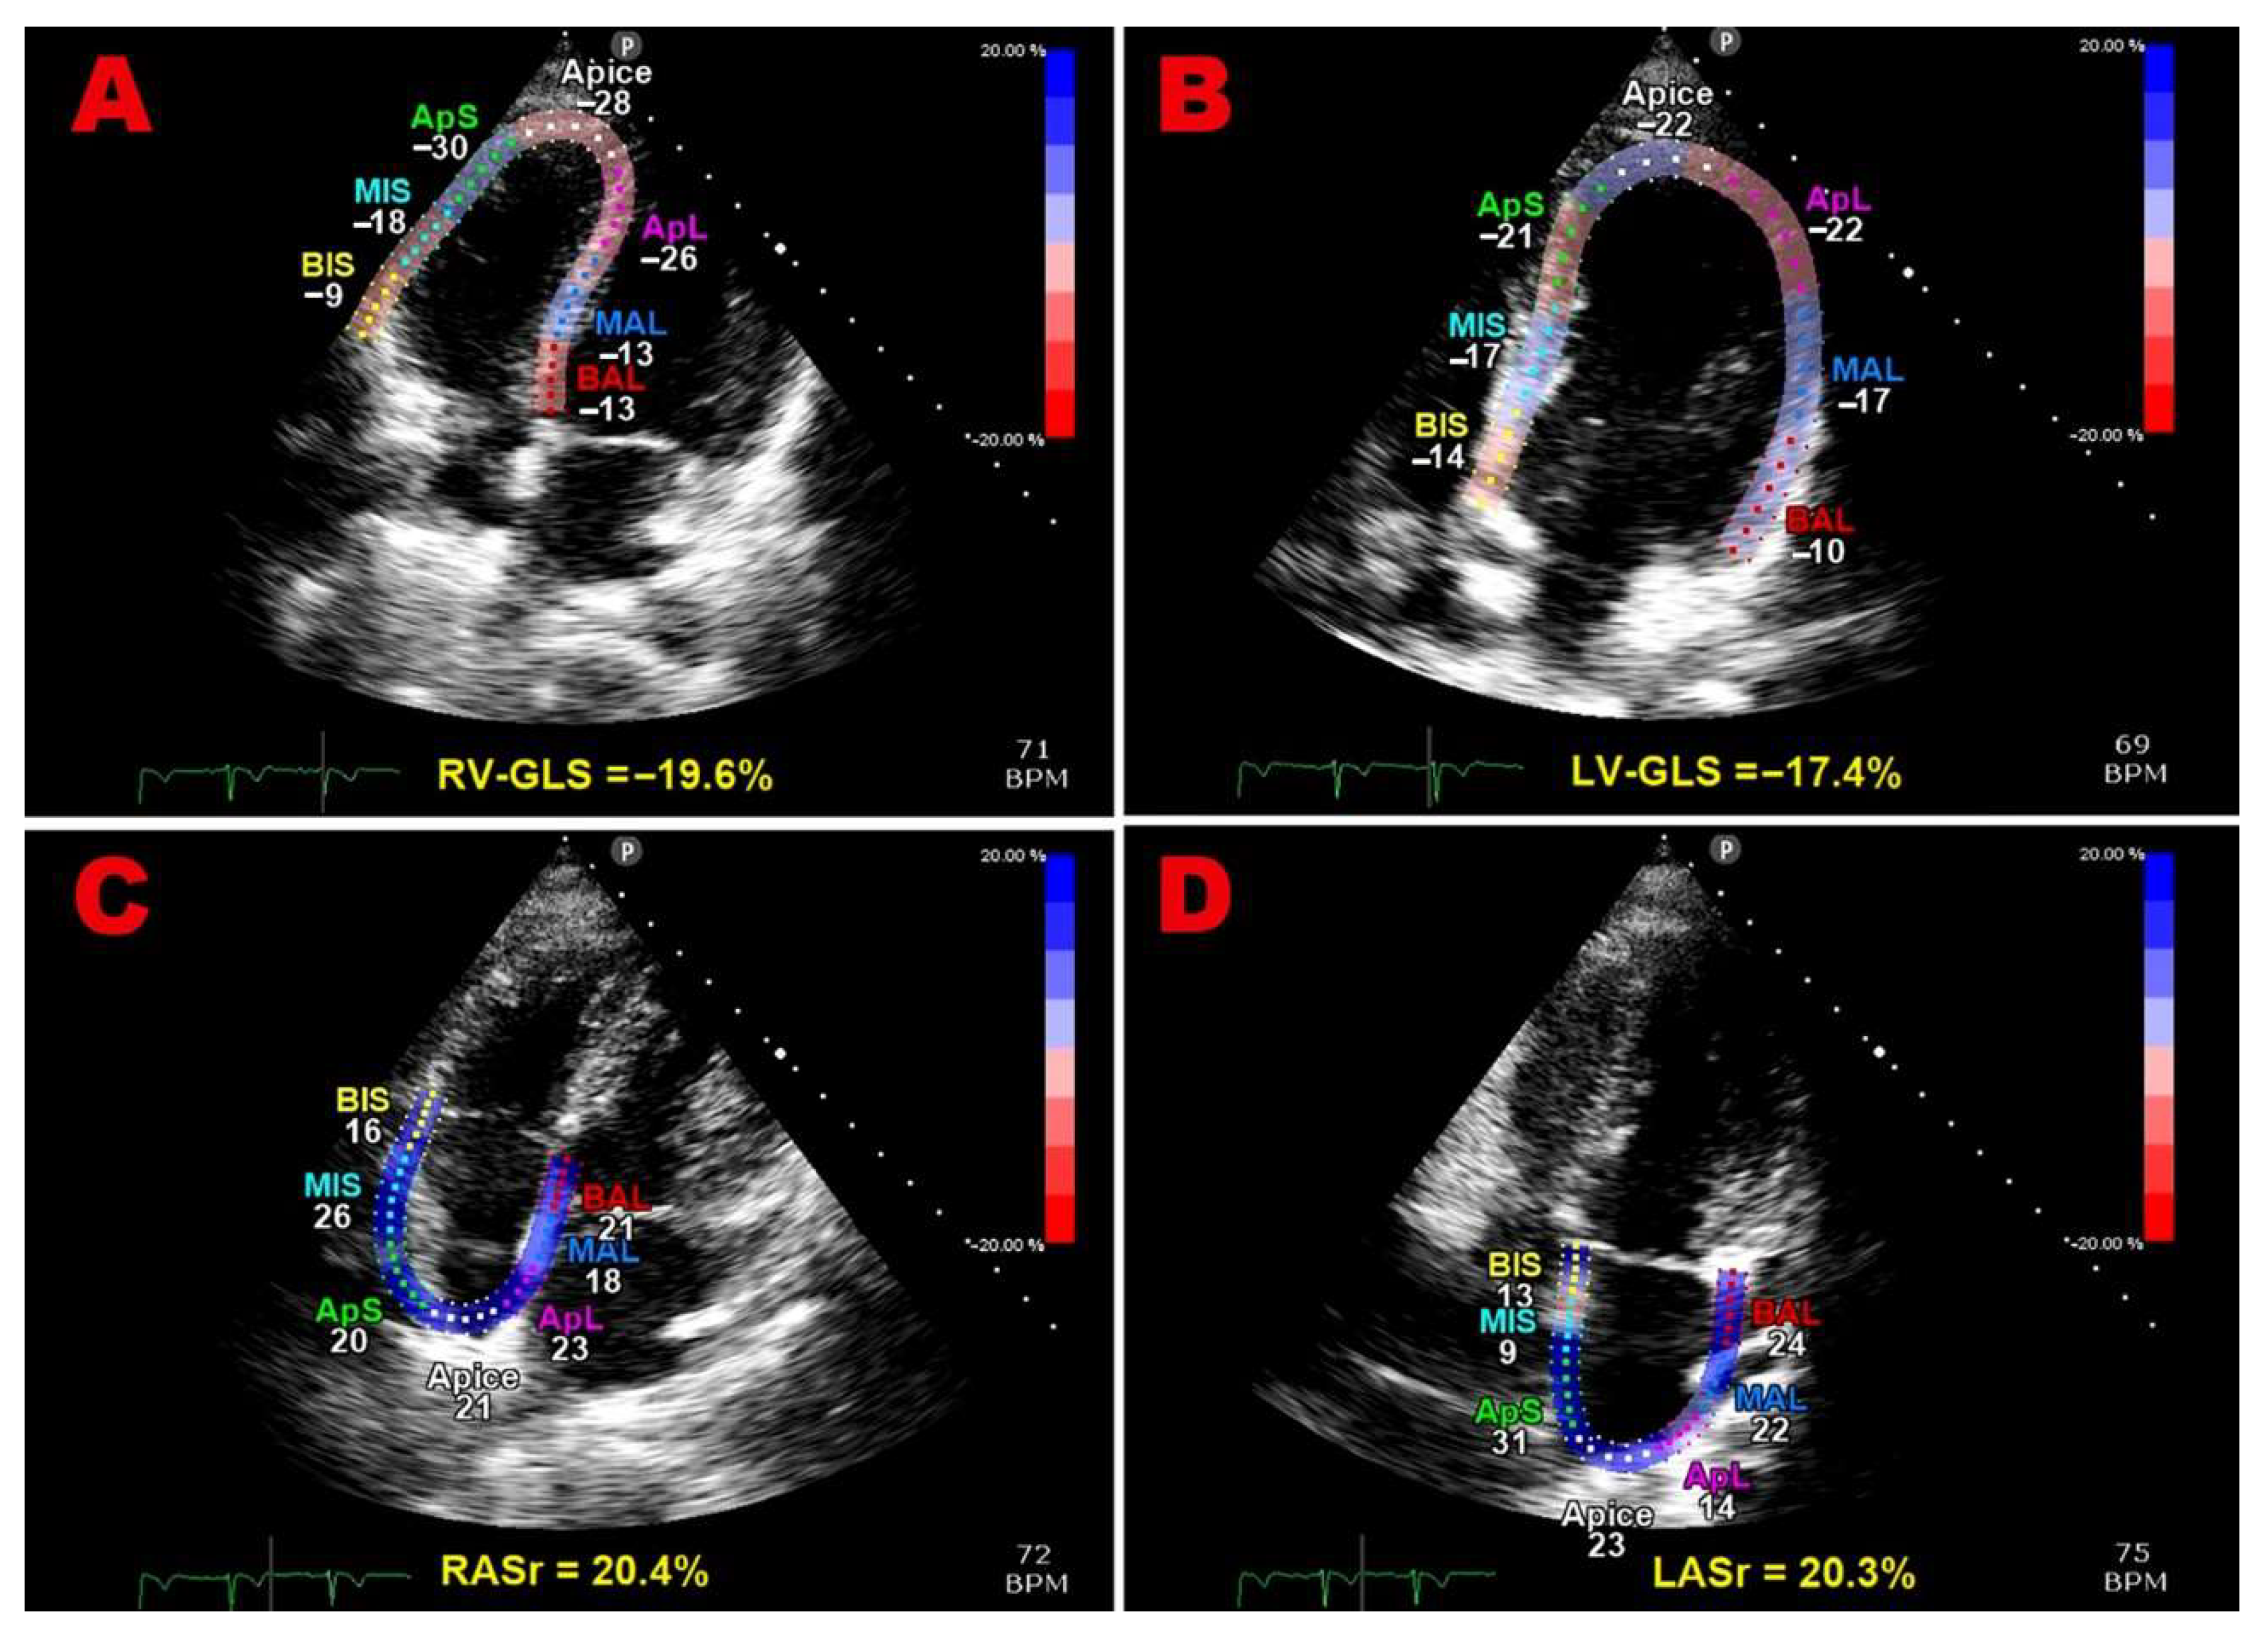

Multipanel Figure 1 illustrates examples of biventricular and biatrial longitudinal strain parameters measured from the apical four-chamber view in a pHDP woman included in the present study.

Figure 1. Examples of biventricular and biatrial longitudinal strain parameters measured from the apical four-chamber view in a pHDP woman included in the present study. All myocardial strain parameters are reduced in comparison to the accepted reference ranges. GLS, global longitudinal strain; LASr, left atrial reservoir strain; LV, left ventricular; pHDP, previous hypertensive disorder of pregnancy; RASr, right atrial reservoir strain; RV, right ventricular.